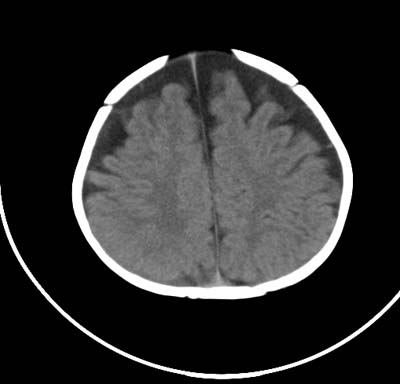

以下是引用影象小泰斗在2008-6-30 15:57:00的发言:[br]双侧额、颞部蛛网膜下腔增宽,纵裂加深, 支持外部性脑积水![br] 双侧基底节点状钙化!

以下是引用jiangjing在2008-6-30 17:19:00的发言:[br]双侧额、颞部蛛网膜下腔增宽,纵裂加深, 支持外部性脑积水![br] 双侧基底节点状钙化![宫内感染形成可能]